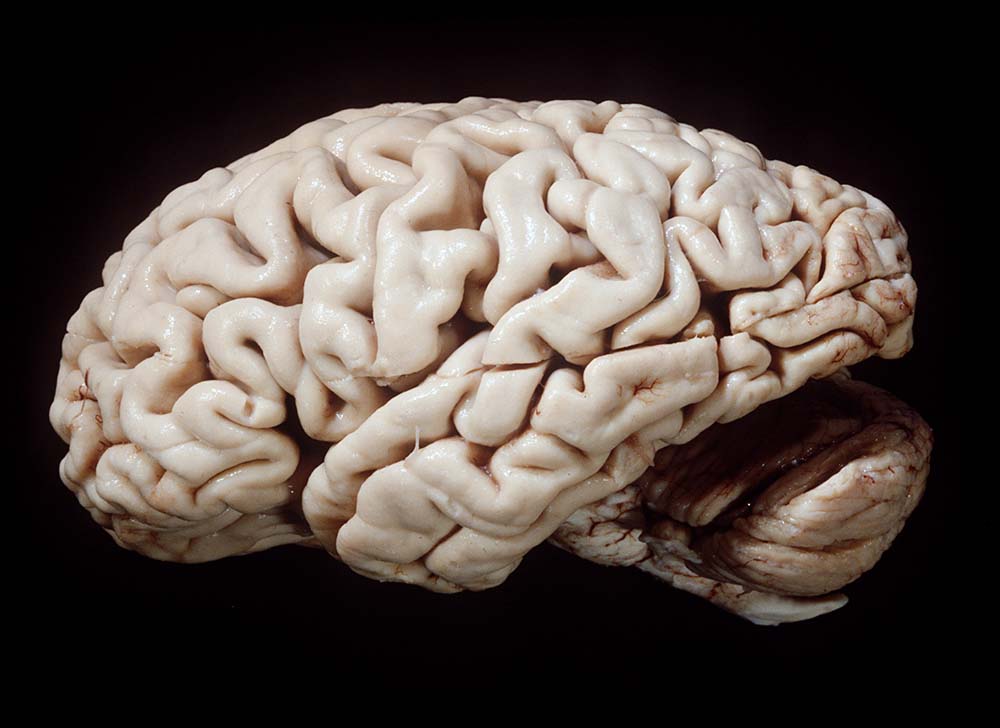

Gehirne von Alzheimer Patienten sind makroskopisch durch eine kortikale Atrophie (vor allem temporo-parietal) charakterisiert. Weiter findet sich meist eine deutliche Atrophie von Hippocampi und Mandelkernen. Diese geht einher mit einem Hydrocephalus internus (e vacuo), wobei vor allem die Temporalhörner der Seitenventrikel betroffen sind.

Makroskopie

Befund

Pathologischer Befund

Normalbefund